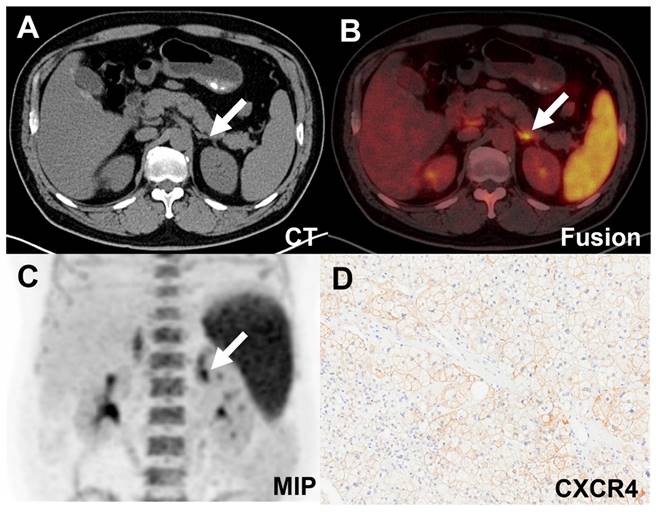

Figure 4

False-positive uptake (SUVmax 11.08, white arrow) in an IHA lesion on [18F]AlF-NOTA-pentixather PET/CT scan. A-C. PET/CT showed increased activity in the left adrenal nodule. D. Expression of CXCR4 was demonstrated in the adrenal hyperplastic tissue.